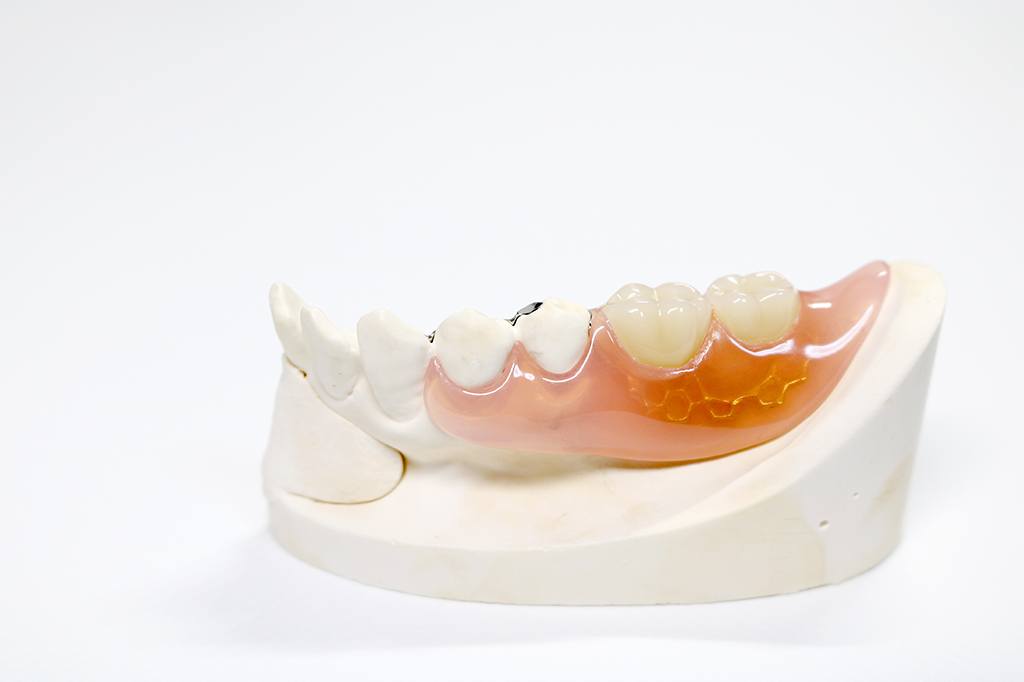

ノンクラスプデンチャー保険適用外

歯ぐきに近い色をした樹脂素材で作られており、薄さと軽さを兼ね備えているため、装着時の違和感が少ないことが特徴です。また、金属のバネを使用していないので、保険診療の入れ歯より目立ちにくく、金属アレルギーの心配もありません。

※症例によっては適用できない場合があります。